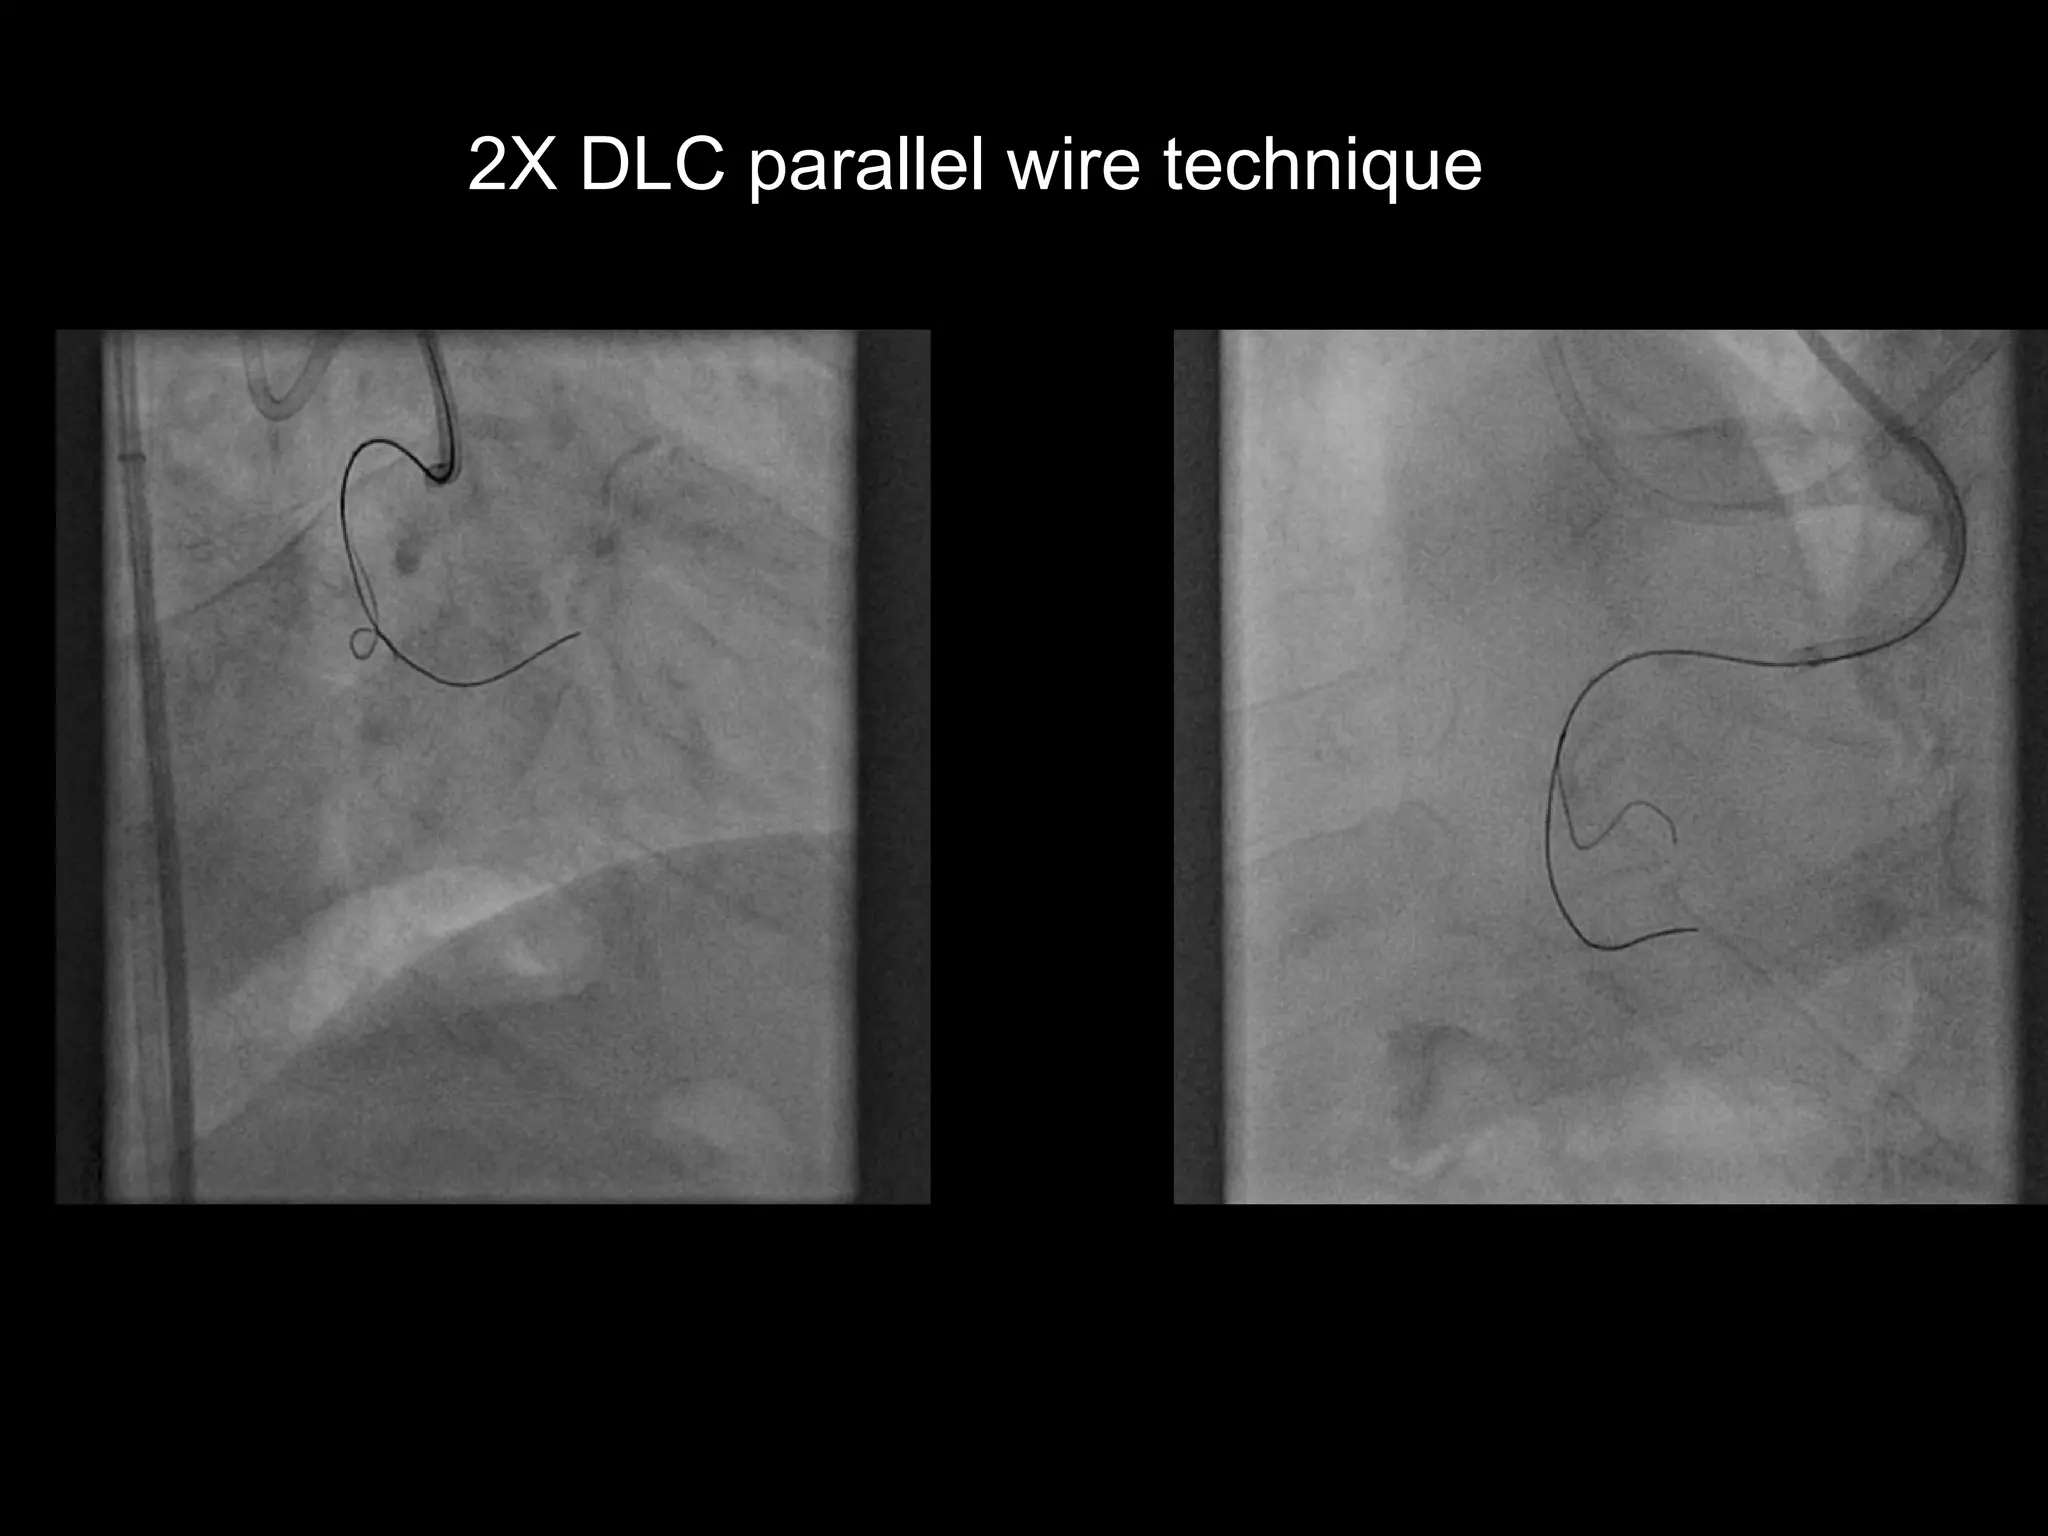

2X DLC parallel wire technique